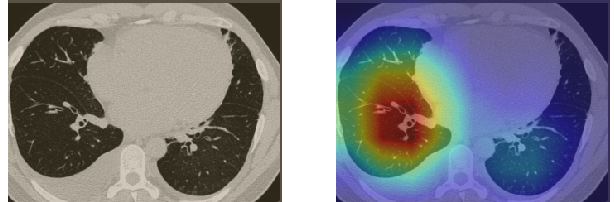

In order to make our models more transparent and provide detailed visual analysis, we present the Grad-CAM localization maps obtained by different models. We consider CT images with COVID-19 abnormalities from the test set of each dataset and highlight the important regions considered for the prediction. For the SARS-CoV-2 dataset we use the Inception V3 model. Figure 13 shows the original CT images and their localization maps. Our model is capable to detect regions that show abnormalities in the CT scans.

In a similar way, we consider classifying the test CT scans from the COVID-19 dataset by the DenseNet169 model and highlight the important regions considered for predictions. We present the original CT images and their localization maps in Figure 13. We can also see that our model is capable to detect the COVID-19 related regions as marked (small square in some images) by expert radiologists.

A wide variety of typical and atypical CT abnormalities have been reported for COVID-19 patients in various studies [58, 59]. So, we tested our models on external CT images extracted from these two publications as they feature typical findings of COVID-19 pneumonia marked by specialists. In order to make sure that not any of the extracted images are unintentionally included in our datasets, specifically the COVID19-CT dataset, we use the model trained on the SARS-CoV-2 dataset. First, the InceptionV3 model is employed to classify the extracted CT images. The model is able to correctly classify the given CT images as COVID-19. Second, in order to interpret the model’s generalization capabilities, we apply the Grad-CAM technique to visualize the regions of abnormalities that are considered. By assessing the different CT images in Figure 15, we can see that the model accurately localizes the disease-related regions. Even more interesting is the fact that the model ignores any specific marks in the images like letters and only localizes the COVID-19 related regions. These visual explanations show the success of our models to learn relevant, generic visual features related to COVID-19 and are capable to correctly classify CT images outside the datasets on which they are trained.